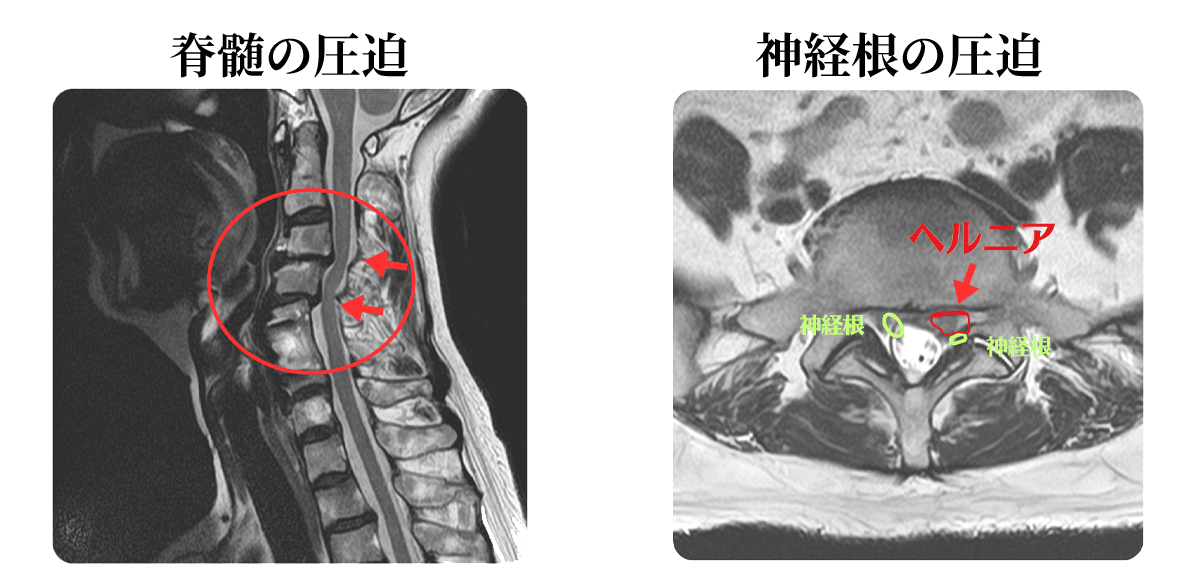

レントゲンでは見えない神経の圧迫が明らかになる!

「しびれ」や「痛み」が神経から来ていると疑われる場合、MRI検査が最も信頼できる診断ツールの一つとなります。

骨だけでなく、その周囲の軟部組織や神経との位置関係を総合的に評価できる点が強みで、神経そのものや、神経を圧迫している椎間板、靭帯などの軟部組織が詳細に描出されます。